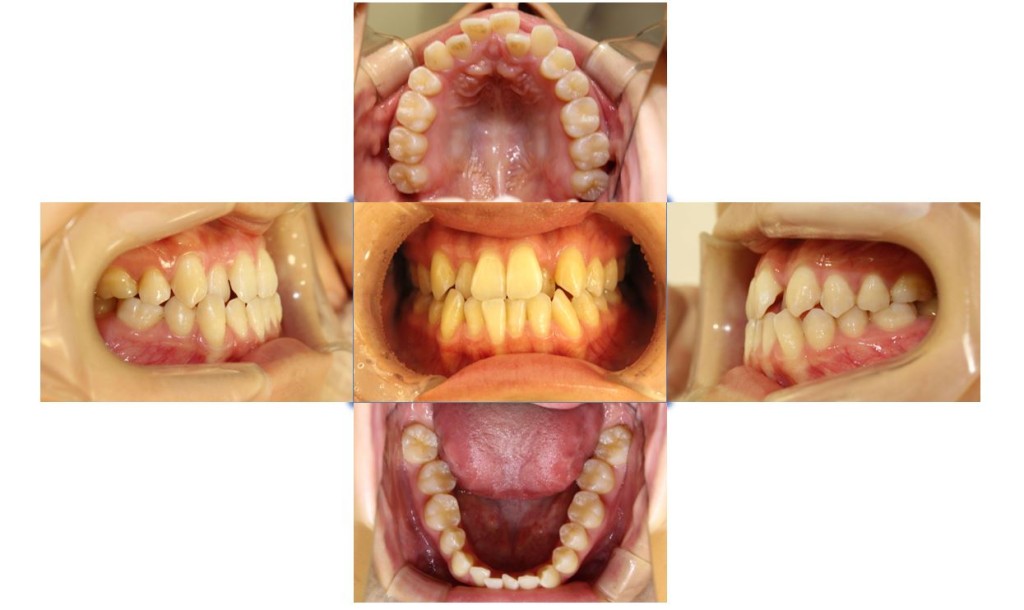

| 主訴 | 下の歯が、上の歯より前に出ていて顎が出ているのが気になる。受け口を治したい。でこぼこもあり歯磨きにしくいので、虫歯予防のためにも綺麗に並べたい。 |

| 治療期間 | 2年2ヶ月(29回) |

| 抜歯 | 有(左上4、左下5、上下親知らず4本) |

| 矯正の装置 | 裏側矯正(舌側矯正) |